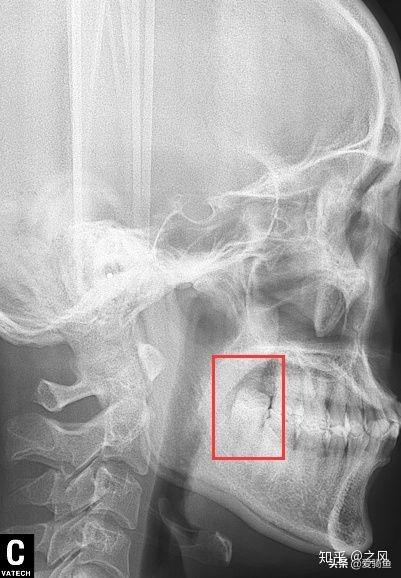

排隊(duì)等待叫號(hào),進(jìn)去后張嘴檢查下,讓去拍片子,應(yīng)該就是我之前去的其他牙診所機(jī)構(gòu)的口掃,這里沒有給我電子照片,下面是以前拍的。

口掃

智齒